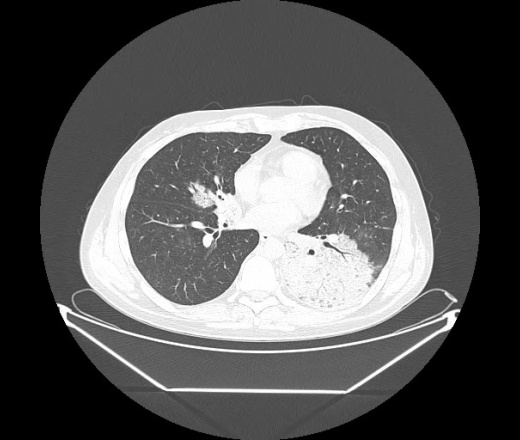

М. 1984 г.р.  Лихорадка 39, кашель , одышка.. и надоевший всем вопрос- "типично ли для ковид?" ( в настоящее время на него обязательно нужно дать ответ в своем протоколе)

На мой взгляд нетипично для ковид: много центрально-расположенных поражений, лобарное поражение нижней доли слева. 50/50

Не типичая картина для ковид.

КТ-признаки двусторонней бактериальной пневмонии.

Все верно, здесь абсолютно нетипичная картина, несмотря на матовое стекло с ретикулярными изменениями, но почему-то  посчитали иначе. Кстати,  "малыша" не заметили)?

Добавил 6 день

Что за малыш? Будущий абсцесс? Не заметил. Только о туберкулёзе подумал

+ 1?  Зона очень похожа была на формирующийся абсцесс, даже по рентгенпризнакам. Еще хотела спросить, но постеснялась. А на контроле видно

да, это я о абсцессе.